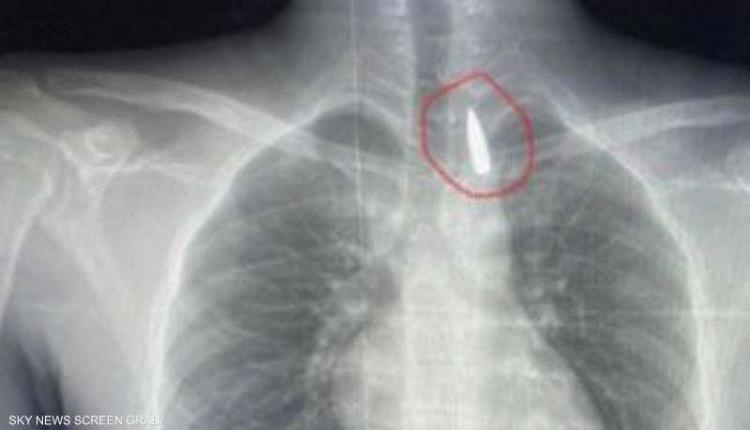

مقذوف استقر في صدره.. إنقاذ حياة مصاب من غزة في مصر

تمكن فريق طبي مصري متخصص بمستشفيات جامعة الإسكندرية من إجراء جراحة دقيقة ونادرة لإنقاذ مصاب فلسطيني من قطاع غزة، بعد استخراج مقذوف استقر قرب الشريان الأورطي بنجاح.

وأوضح عميد كلية الطب جامعة الإسكندرية ورئيس مجلس إدارة المستشفيات الجامعية تامر عبد الله، أن فريق من أطباء قسم جراحة القلب والصدر والتخدير والمعاونين تكمنوا من إجراء جراحة دقيقة بالغة الخطورة لأحد المرضى من قطاع غزة، والذي كان قد تعرض لإصابة بطلق ناري منذ فترة، استقر المقذوف على إثرها داخل تجويف القفص الصدري قرب الشريان الأورطي.

مبينا أن الفريق الطبي نجح، رغم دقة الحالة وتعقيدها، في استخراج المقذوف بأمان بعد عملية جراحية استمرت عدة ساعات داخل المستشفى الجامعي الجديد، حيث خضع المريض بعدها للرعاية الطبية اللازمة، مؤكدا أن حالة المريض حاليا مستقرة وتحت المتابعة الدقيقة من الفريق المختص.